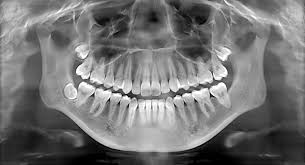

Panoramic X-rays capture a wide-angle view of the entire mouth, including the teeth, jaws, and surrounding structures. This comprehensive imaging is essential for identifying issues that might not be visible with standard intraoral X-rays, such as impacted teeth, jaw disorders, and sinus problems.

These X-rays provide clear, detailed images, aiding in the diagnosis of complex dental conditions. Dentists can detect fractures, cysts, tumors, and other abnormalities that could significantly impact oral health. This enhanced clarity ensures accurate diagnosis and effective treatment planning.

Panoramic X-rays are indispensable for planning various dental treatments, including orthodontic procedures, dental implants, and extractions. Having a detailed image of the mouth helps dentists devise precise and effective treatment plans, ensuring the best possible outcomes for patients.